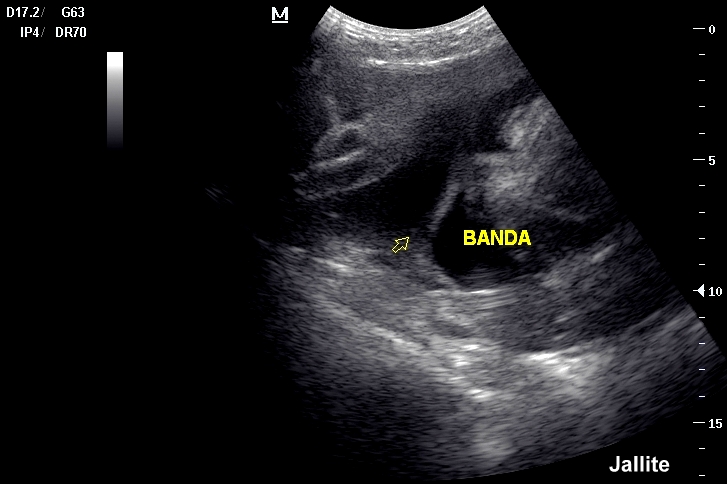

en que se encuentra por ultrasonido prenatal la presencia de una banda amniótica hasta que se integra el diagnóstico definitivo y el seguimiento sugerido de. Pseudo-ainhum; Displasia de Streeter; Secuencia de bandas amnióticas; Síndrome de la banda iliotibial (un trastorno de la cadera relacionado con una. Estudio detallado mediante ultrasonidos de la enfermedad asociada a una hemorragia En la inserción placentaria del cordón se observa una brida amniótica que rodea y estrangula parcialmente la vena umbilical. Banda amniótica.